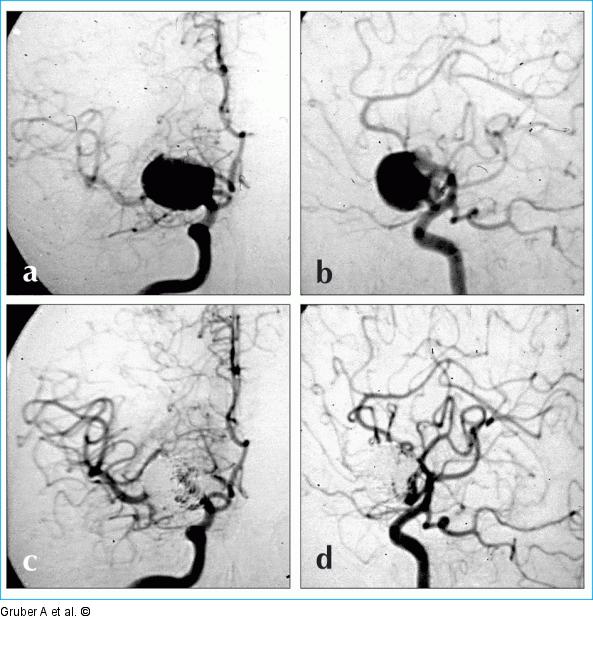

Abbildung 4a-d: Coil-Embolisation Coil-Embolisation. Angiogramme der A. carotis interna in a.p. und seitlicher Projektion (a, b) vor und (c, d) nach endovaskulärer Therapie eines rupturierten Mediabifurkationsaneurysmas rechts. |

Coil-Embolisation. Angiogramme der A. carotis interna in a.p. und seitlicher Projektion (a, b) vor und (c, d) nach endovaskulärer Therapie eines rupturierten Mediabifurkationsaneurysmas rechts. |